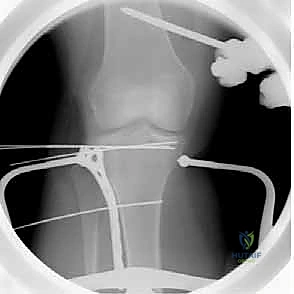

التدخل الجراحي (ORIF): خطوة بخطوة مع الأستاذ الدكتور محمد هطيف

التثبيت الداخلي المفتوح (Open Reduction and Internal Fixation - ORIF) هو الإجراء الجراحي القياسي لكسور الهضبة الظنبوبية الجانبية المزاحة. بفضل خبرته الواسعة وتدريبه المتقدم، يُجري الدكتور هطيف هذه العمليات بدقة متناهية.

2. التخدير والتموضع

تُجرى العملية عادة تحت التخدير النصفي (Spinal Anesthesia) أو العام. يتم وضع المريض على طاولة العمليات الإشعاعية، ويُستخدم جهاز الأشعة المرئية (C-arm) داخل الغرفة لمراقبة العظم أثناء الجراحة.